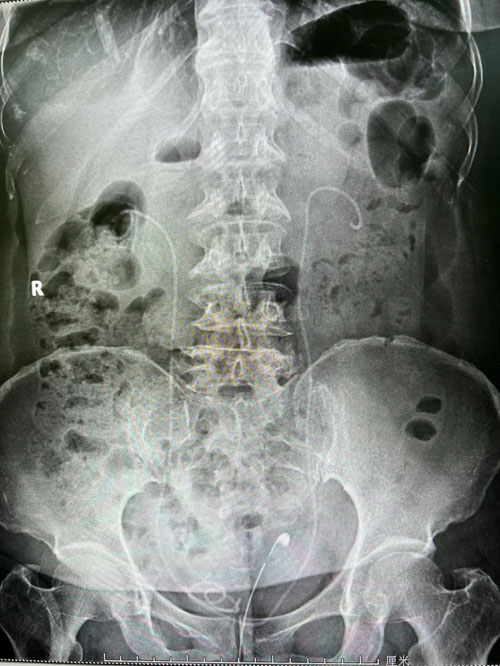

患者術(shù)前CT

副院長(zhǎng)程廣舟和程波副主任認(rèn)真閱片、分析病情,認(rèn)為患者手術(shù)難點(diǎn)在于,患者雙側(cè)結(jié)石,且結(jié)石體積大、質(zhì)地硬,預(yù)計(jì)碎石清石會(huì)耗費(fèi)較長(zhǎng)時(shí)間;患者既往結(jié)石手術(shù)史,解剖結(jié)構(gòu)復(fù)雜,腎臟積水不重,穿刺難度大;患者合并糖尿病,術(shù)前感染較重,手術(shù)過(guò)程中,腎盂壓力增大,細(xì)菌進(jìn)入血液引起菌血癥甚至膿毒血癥的風(fēng)險(xiǎn)高,時(shí)間越長(zhǎng),風(fēng)險(xiǎn)越大。雖然手術(shù)難度大,但考慮患者的經(jīng)濟(jì)條件,經(jīng)過(guò)全科討論,決定行一期雙側(cè)手術(shù),術(shù)中根據(jù)情況變更手術(shù)方案。

在程廣舟副院長(zhǎng)的指導(dǎo)下,程波副主任為患者實(shí)施手術(shù)。患者結(jié)石質(zhì)地堅(jiān)硬,碎石困難,在麻醉醫(yī)師與手術(shù)室護(hù)士的通力配合下,該患者順利完成雙側(cè)“無(wú)管化”經(jīng)皮腎鏡碎石取石術(shù)。從精準(zhǔn)穿刺到擴(kuò)張,再到手術(shù)結(jié)束,僅僅用了1個(gè)半小時(shí)。手術(shù)過(guò)程中,麻醉醫(yī)生密切觀察患者情況,術(shù)后患者順利復(fù)蘇,術(shù)后恢復(fù)良好,未出現(xiàn)發(fā)熱情況,術(shù)后復(fù)查腹部平片未見(jiàn)結(jié)石殘留,患者及家屬非常滿意。